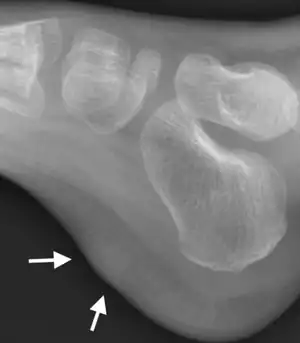

| X-ray foot: Fibrous hamartoma of infancy | |